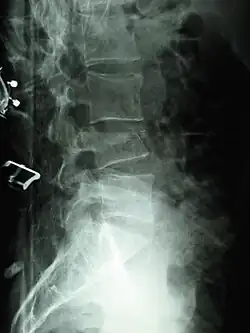

X-ray of the lumbar spine with a compression fracture of the third lumbar vertebra. -